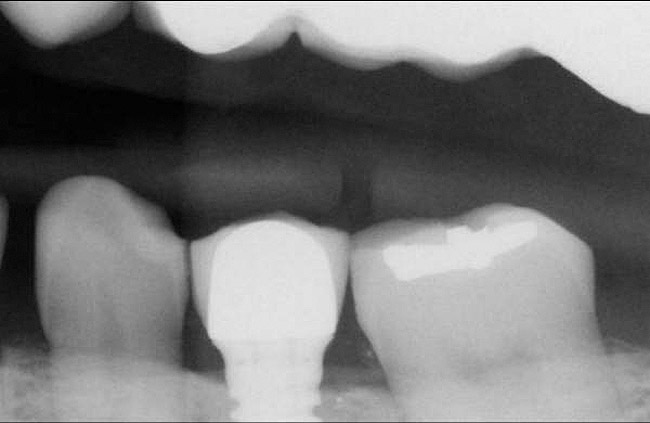

There are several ways to diagnose periodontitis. In addition to soft tissue evaluation, one of the most common and accurate methods is to use a periodontal probe in affected areas and record probing depths. Bleeding on probing is another indication of unhealthy periondontal tissues. Radiographs can be used, but they have limitations in initial diagnosis because bone loss is typically associated with severe and chronic periodontal disease; therefore, radiographs are better used to confirm diagnosis. However, vertical bitewings taken over time can be placed side-by-side to detect even slight differences in contrast.

Figure 2  Vertical components of crown height space for a cement-retained restoration.

Figure 2